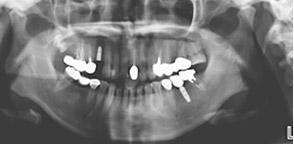

天津市中诺口腔医院(全国连锁·国家二级口腔专科医院)“立得用”种植体系对手术精准度要求更高,采用口腔CBCT技术诊断,从任意角度、任意方位,立体化观察牙槽骨情况,确定科学种植位置,设计出科学种植方案,立种、立用,生物相容性更好,更稳定牢固。

根据顾客牙槽骨密度、高度、宽度,在数字化辅助下自动避开血管和神经,以较短的时间和1微米的创口精度,精准快速种下每一颗种植体,当天做种植牙,当天就能戴牙。

术前 · 精确诊断 在线预约,享免费检查 >>

• 1拍片确诊

• 2确定方案

• 3三维重建